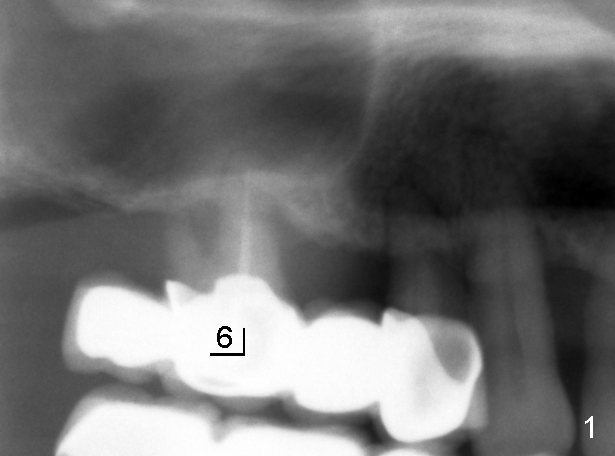

十天前我们初步讨论徐博那个疑难病例:右上4-7牙桥两到三度松动,如果问题在第一磨牙(图一:6),在4与5之间切断牙桥(图三虚线),拔除磨牙后即刻植牙(图三:大的红框)。虽然那里上颌窦底骨壁均为厚2mm左右,但是在那个磨牙牙根尤其是鄂侧根根尖处骨壁可能不止2mm,好像拱形(图二箭头,与图一对比)。所以第一磨牙处可以植入8x11mm植牙,不过需要做sinus

十天来对以上设计有双重心情,尤其是对那虚无缥缈的上颌窦里骨质(图二箭头),内心不踏实。